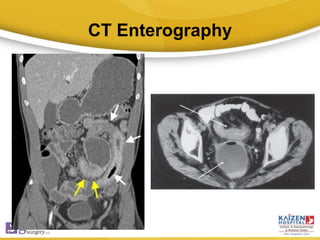

CT Enterography